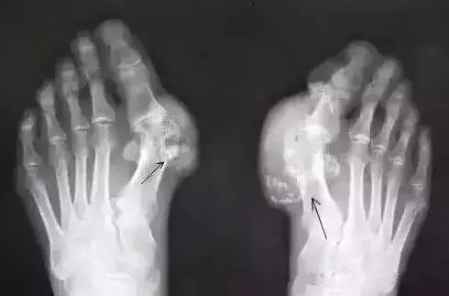

痛风在男性中较为多见,拇趾是最常见的受累区域,50%~70%初次发病发生于此。90%的痛风患者在其一生中的某个时期会发生第一跖趾关节受累。其他可能受累的足部区域有足背部、足跟以及踝部。除了累及关节之外,尿酸结晶还可以沉积在皮下,被称作痛风结节。

尿酸怎么会高?医生说是因为喝酒过多、吃了太多高蛋白食物。很多人听了马上控制饮食,可是不管怎么忌口,该发作它还是痛。为什么会从大脚趾头开始痛,后期还会出现关节畸形?

其实这也是肾虚的一种症状,因为肾的过滤功能减弱了,血液里的酸毒排不出去,随着血液循环流动。大脚趾关节是人体的最末梢关节,酸毒的结晶体最容易积聚在这里,也有的人是大拇指关节痛,都是同样的道理。

如果你不去调整肾脏,恢复它的过滤功能,酸毒结晶长期挤压关节,最后关节不能正常活动,出现变形了。所以痛风患者不仅要改变饮食习惯,更关键在于恢复肾脏的机能,提高过滤能力,把酸毒排出体外才不会再复发。